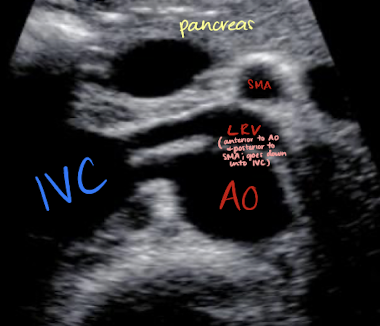

LRV and RRA locations

LRV

anterior to AO; posterior to SMA

runs from left kidney to IVC

RRA

posterior to IVC (excuse me)

runs from AO to RK